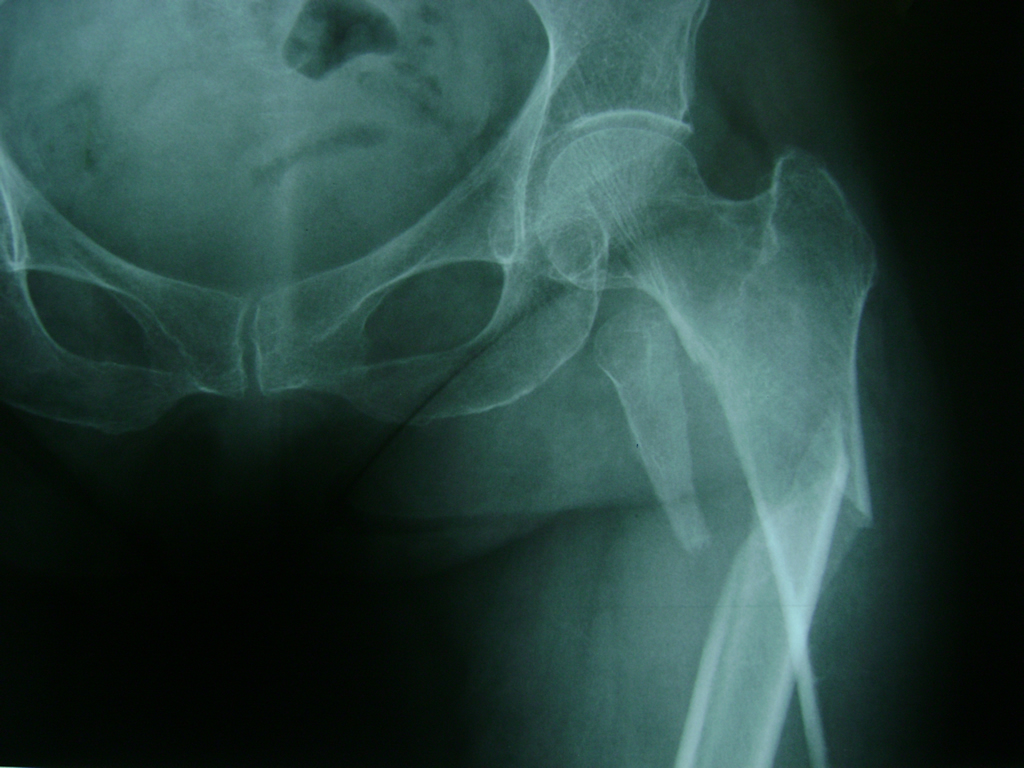

La cirugía de fractura de cadera se realiza para reparar una ruptura en la parte superior del hueso del muslo. Este hueso se denomina fémur.

Es parte de la articulación coxofemoral. Si una fractura de cadera no recibe tratamiento, es posible que deba permanecer en una silla o en la cama.

Esto puede llevar a otros problemas de salud potencialmente mortales, sobre todo si usted es una persona mayor.

A menudo se recomienda la cirugía para reparar la fractura debido a dichos riesgos.